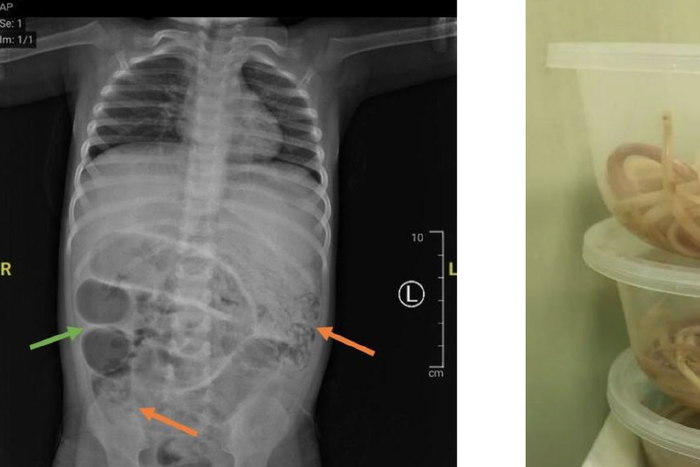

Awalnya, dokter menduga ada sumbatan pada saluran cerna pasien. Setelah dilihat dari Hasil CT scan, pasien ternyata mengalami kondisi ileus obstruktif atau penyumbatan usus yang membuat saluran pencernaan tidak bisa berfungsi optimal.

“Kemudian diperiksa CT scan, memang menggambarkan suatu kondisi yang disebut ileus obstruktif, yaitu buntunya saluran pencernaan akibat sesuatu,” kata Nyoman.

Perut anak di Jember yang dipenuhi hewan ini hingga tak bisa BAB selama seminggu. Ia lalu dibawa ke RSD dr Soebandi.

(Dok RSD dr Soebandi Jember via Kompas.com)

Dokter menyebut pasien sempat muntah dan mengeluarkan cacing dari mulutnya saat menjalani perawatan di ruang rawat inap. Peristiwa itu sontak membuat tim medis syok.

Operasi Ungkap Usus Penuh Cacing

Setelah diskusi itu, tim dokter memutuskan untuk segera melakukan operasi karena kondisi pasien sudah mengganggu fungsi pencernaan dan pernapasan.